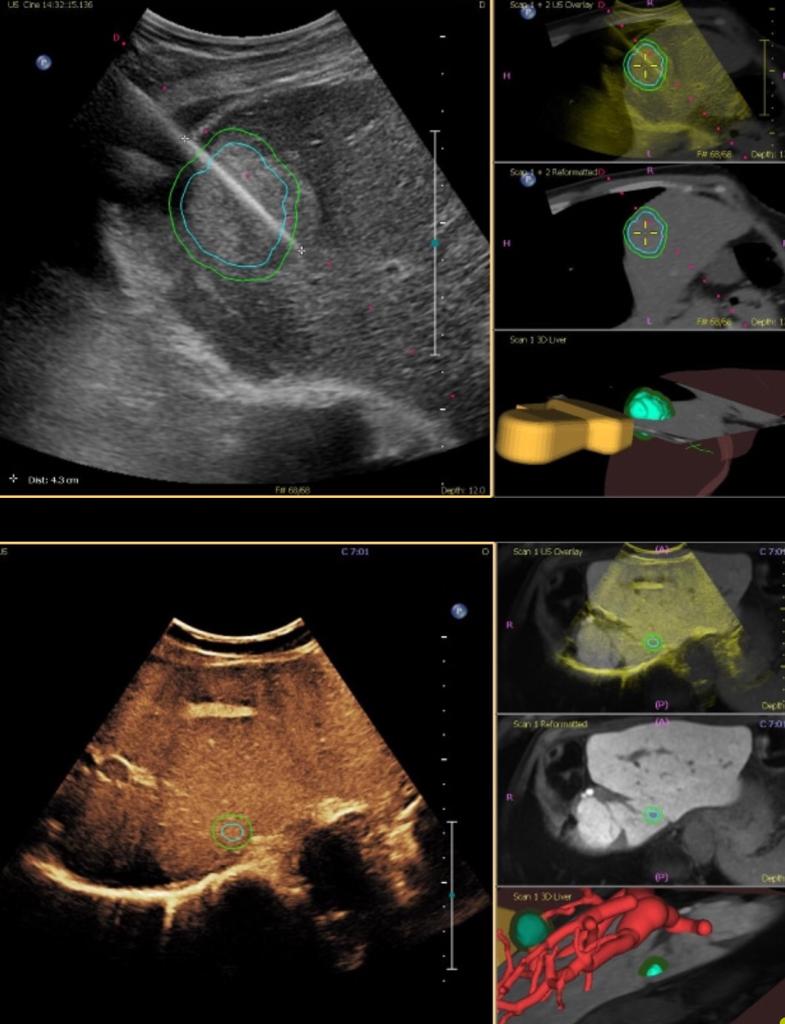

Girişimsel radyolojide yaygın olarak tercih edilen bir diğer yöntem ise damar dışında uygulanmaktadır. Tıbbi alanda non-vasküler girişim olarak bilinen bu yöntemlerde; kistler, apseler, böbrek ve safra yollarında yaşanan sağlık problemlerine müdahale imkanı sağlanmaktadır. Damar dışında yaşanan rahatsızlıklar için daha hızlı ve kolay bir müdahale olarak bilinen girişimsel radyoloji, tümör gibi ileri durumlarda dahi tercih edilebilmektedir. Yakma işlemleri, çeşitli organlardan biyopsi alma işlemleri, kistlerin ve apselerin alınması gibi durumlarda damar dışı olarak non-vasküler girişimler tercih edilmektedir.